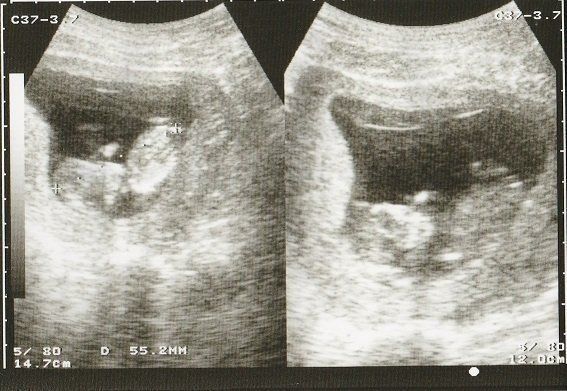

妊娠9週目のエコー写真 何となく人の形?

落花生のように真ん中がくびれた胎児の形が見えるようになってきました。

妊娠10週目のエコー写真 大きな塊に

まだまだ「赤ちゃんだなあ」とは思えない形の画像です。